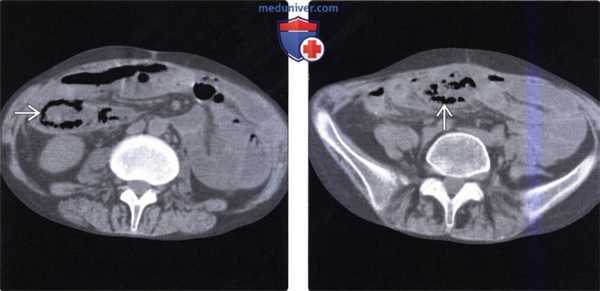

(Слева) На аксиальной КТ без контрастного усиления определяется распространенная инфильтрация брыжейки трансплантата тонкой кишки наряду с утолщением стенки кишки. Эти изменения являются частыми неспецифическими находками у реципиентов трансплантата тонкой кишки.

(Справа) На аксиальной КТ без контрастного усиления определяются уровни «жидкость-жир», свидетельствующие об ограниченном хилезном асците с наличием жидкости между петлями трансплантата тонкой кишки. Утечка жидкости из лимфатических капилляров обычно разрешается с течением времени по мере восстановления их целостности, однако в некоторых случаях может потребоваться чрескожное дренирование с целью удаления жидкости.

(Слева) На КТ без контрастного усиления определяется дилатация аллотрансплантата, а также утолщение его стенки и пневматоз, что является крайне подозрительным признаком инфаркта трансплантата.

(Справа) На КТ без контраста у этого же пациента определяется пневматоз ближайших отделов трансплантата тонкой кишки. При эндоскопическом вмешательстве (через илеостому) не было обнаружено изменений внешнего вида слизистой оболочки. Пневматоз стенки трансплантата тонкой кишки встречается нередко и может быть результатом инфаркта, приема лекарственных препаратов, применяемых для профилактики отторжения, обструкции кишечника или иных «доброкачественных» причин.